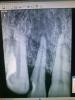

marffa Опубликовано 8 ноября, 2013 Поделиться Опубликовано 8 ноября, 2013 Здравствуйте, коллеги! Пожалуйста, помогите...... на картинке 4.6 - огромная гранулема (сори за paint-Rg... не имею возможности сделать фотографию). Пациент мнительный, скользкий, дотошный и настойчивый! УДАЛЯТЬ НЕ ХОЧЕТ!!! Готов сам закупать материал и пилюли, только чтобы я ему помогла! Около 5 лет такая картина: из десны постоянно выдавливает гной самостоятельно, полощит солью. На снимке 5-летней давности гранулема чуть поменьше. лечен рф + фотополимер (каким-то образом там оказался). Перкуссия слабо+. В частной стом. клинике ему сказали, что можно в зубо-десневой карман каким-то образом прикрепить какой-то там катетер, чтобы выходил гной. Внимание вопрос: что это за такой катетер? (или имели ввиду дренаж из перчаточной резины) и куда его совать? в з.-д. карман? Подойдет ли такое лечение:1) Таб. Метронидазол 0,25 (1т. 2р. в день/ 10 дней)2) Аэрозоль Аминитрозол (нитразол) по 1 дозе местно 2р. в день/ 15 дней3) свечи ректально Метронидазол или Тержинан по 1 св. на ночь/ 10 дней Ах, да! Он еще захотел направление на анализ крови по количеству трихомонад перед лечением и после курса лечения (и знает же откуда-то, что это у него ротовая трихомонада!!!!!!!) и какой лучше будет сделать анализ? р.с. я работаю в гос. п-ке Ссылка на комментарий

marffa Опубликовано 8 ноября, 2013 Поделиться Опубликовано 8 ноября, 2013 он уже больше 5-ти лет знает, что его удалять надо... НО: "он же у меня не болит" Ссылка на комментарий

marffa Опубликовано 8 ноября, 2013 Поделиться Опубликовано 8 ноября, 2013 а то, что гной оттуда, как из водонапорной башни (при надавливании зондом на маргин. десну течет рекой), так это его мало волнует Ссылка на комментарий